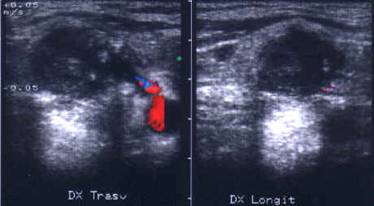

Lobul drept, proiectie trasversala si longitudinala.

Femeie de 29 ani. Nodul de consistenta dura in lobul

drept si istm.

Ecografia: nodul cu margini difuze in lobul drept si istm, care deformeaza

conturul anterior al glandei, structura parenchimatoasa, neoomogena, hipoecogena.

Prezenta de linfonoduli laterocervicali.

Citoaspiratia: carcinom papilar.

Examen histologic: carcinom papilar plurifocale varianta foliculara.